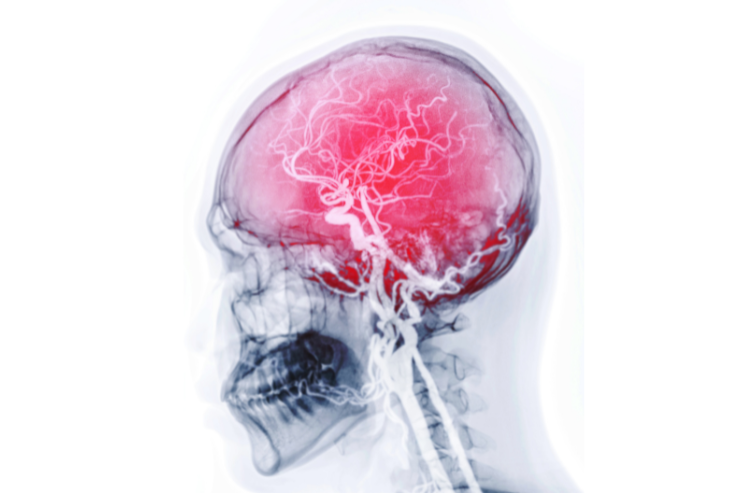

Carotid Angiography

Carotid Angiography is a diagnostic imaging procedure that uses contrast dye and X-ray to visualize the carotid arteries in the neck. It helps identify blockages or narrowing that could increase the risk of stroke. This procedure is crucial for evaluating blood flow to the brain and guiding treatment options to prevent cerebrovascular events.